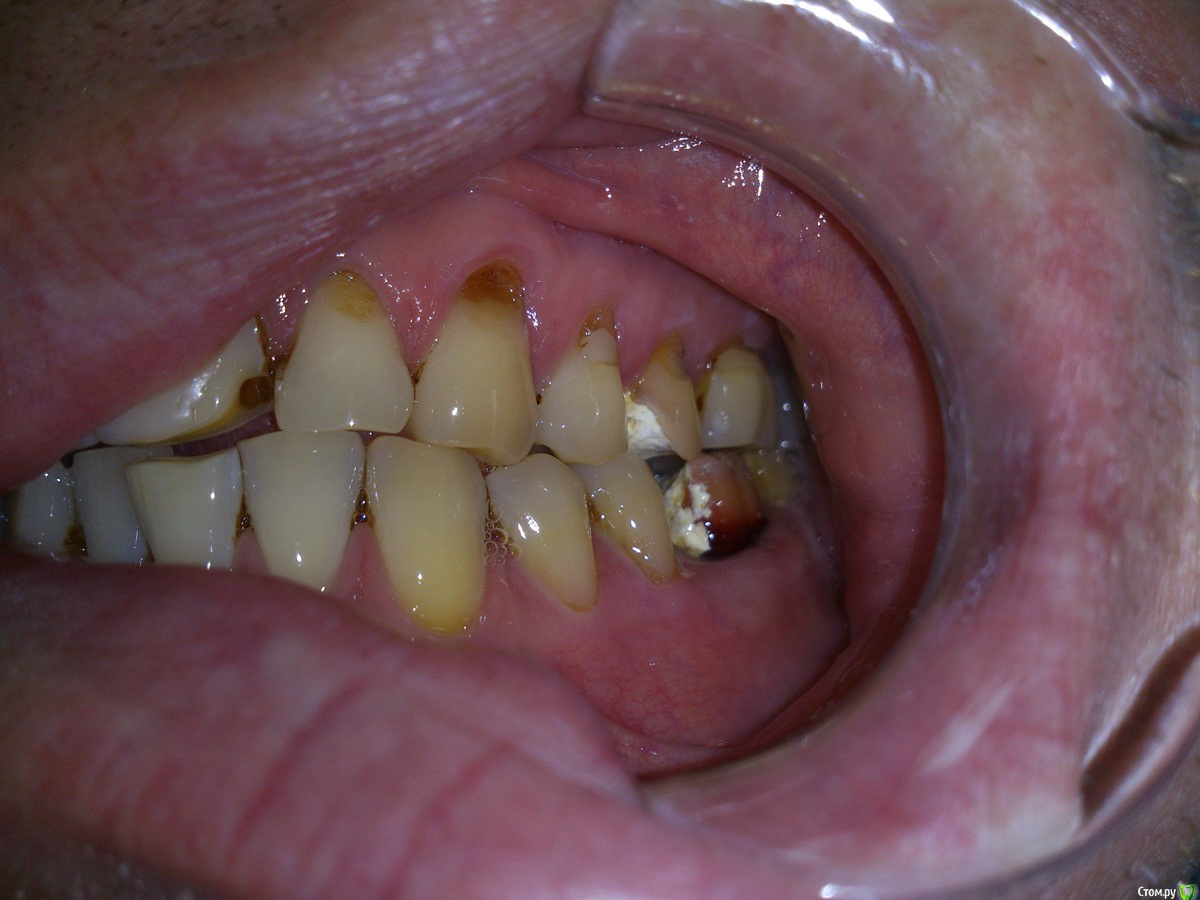

Sampson Опубликовано 7 февраля, 2016 Поделиться Опубликовано 7 февраля, 2016 Если без тотала.1)Снимок. Уз чистка2)Стераемость 13.23/33.43.Востанавливаем клыковую направляющую.3)Эндолечение и попутное поднятие прикуса на накусочных площадках. 4)Времянки Ссылка на комментарий

Ronin Опубликовано 7 февраля, 2016 Поделиться Опубликовано 7 февраля, 2016 Решение оптимальное, как сказал коллега выше, восстановить фронт и клыковое ведение, но как ограничиться этим, ведь бока тоже нужно делать.. там же эндо, как я понял и так делается, одного моляра нет?! реставрации композиционные что ли? Надо учитывать "стискивание" , разломает потом эти зубы и все, плюс расхождение зубов тоже есть, перегрузка, не забудем и про пародонтальный комплекс, высоту поднять, если нужно, предварительно определив, хотя высота, как мне кажется в порядке, но могу ошибаться, на завершающем этапе обязательно каппу, ношение максимальное время! Здесь важно хуже не сделать, если нет уверенности в стабильном результате, ибо не навреди... Если уверенны, то только в путь))) Ссылка на комментарий

SanderS Опубликовано 8 февраля, 2016 Автор Поделиться Опубликовано 8 февраля, 2016 те что после перелечивания естественно будут покрываться коронками, нижний моляр имплантат, если пришеечные дефекты реставрировать композитом при условии восстановления клыковой направляющей + каппа, не повыпадают ли они? Высота у него вроде не снижена, за счет компенсации. Ссылка на комментарий

Ronin Опубликовано 8 февраля, 2016 Поделиться Опубликовано 8 февраля, 2016 те что после перелечивания естественно будут покрываться коронками, нижний моляр имплантат, если пришеечные дефекты реставрировать композитом при условии восстановления клыковой направляющей + каппа, не повыпадают ли они? Высота у него вроде не снижена, за счет компенсации.Пломбы не простоят долго, здесь даже подсказка, что клиновидные дефекты, повсеместно, что перегрузка, упругие деформации в действии имеют место быть. Как временное мероприятие, если средств нет пока заниматься, но лучше уточнить высоту и оставить все на временных до возможности финансово заняться, или билдап сделать на боковых из композита самостоятельно или по вакс-апу, лучше второе. Ссылка на комментарий

Ronin Опубликовано 8 февраля, 2016 Поделиться Опубликовано 8 февраля, 2016 Обратите внимание на 47, если имплантат планируете, то решите пародонтологически страгию, чтоб потом благополучно не расстаться с импл и зубом, 35,36,37 - аналогичная ситуация, пародонтология.Если мероприятия все же будут минимальны, то всегда каппа, максимальное ношение уже сейчас, если не будет реконструкции жевательных плоскостей Ссылка на комментарий